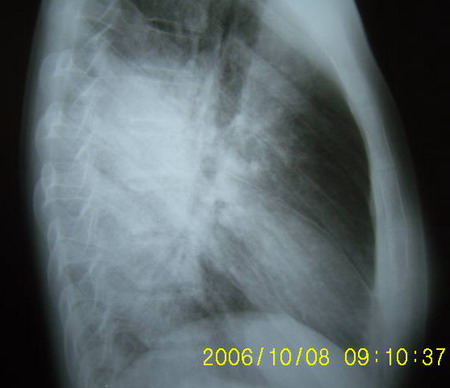

标题: X1082:胸部平片,请会诊

男 18岁 咳嗽 胸痛3天 无咳血 发烧。

主要双肺下叶背段病变,边界不清。

考虑:浸润型肺结核,建议查血象及血沉。

诊断:肺炎

依据:病变跨叶双侧发病,下叶为主,叶间裂增厚,显影,发病时间短,症状不明显可见于年轻患者

双肺中下野片状阴影,密度不均,边界模糊,患者年轻,发病时间短,首先考虑炎症,建议抗炎后复查

双肺部分实变,以渗出为主---大叶性肺炎,治疗复查。

双肺门周围磨玻璃样病变 对称发生 典型的蝶翼征 中央型肺水肿

双肺中下野片状阴影,密度不均,边界模糊,患者年轻,发病时间短,首先考虑大叶性肺炎,建议抗炎后复查请补充相关病史以排除肺水肿结核

考虑肺炎,请结合临床抗炎治疗后短期复查。临床体症不太支持肺水肿。

两肺蝶翼状影:肺水肿.问一下病史,有否农药接触史.

影像与临床表现明显不符[临床表现轻]------支原体肺炎

两中下肺野示大片状密度增高影,边缘模糊。

考虑:1、肺水肿,在问问病史有无其它接触史。

2、支原体肺炎,建议治疗后复查。

两中下肺大片状阴影,边缘模糊,密度较均匀,心脏大小形态无异常,首先考虑两下肺炎,建议结合临床及病史排除肺水肿。

两肺下野大片阴影,边缘模糊,密度尚均匀,考虑大叶性肺炎,建议查wbc和血沉,并抗炎治疗后复查

肺泡蛋白沉着症,依据:肺炎应发热血象升高明显,肺泡蛋白沉着症表现往往与临床不符,表现重临床轻,肺水肿应心脏增大与本病鉴别点

本病人特点1/年龄小病史短2多叶发病心膈角存在肺野中外带病变更著3/无胸腔积液心脏无形态改变4病人无咳血无呼吸困难 因此肺水肿/肺出血病变可除外,暂时先考虑常见的肺炎,先消炎治疗后复查或仔细追问兵史